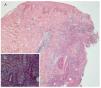

Reporte del casoSe trata de una mujer de 52 años con diagnóstico de CU de 10 años de evolución. Como única manifestación extraintestinal presentaba artritis periférica. Debido a la presencia de displasia de alto grado en biopsia obtenida por colonoscopia, fue sometida a una proctocolectomia con reservorio ileoanal e ileostomía en asa. El periodo posoperatorio de la paciente transcurrió sin complicaciones y se egresó a los cinco días. Seis semanas después de la cirugía, la paciente refirió un dolor intenso en el área periostomal. A la exploración se observó una gran úlcera que rodeaba el estoma con secreción purulenta y necrosis en los bordes (figura 1). Ésta se trató inicialmente como una falla en el manejo del estoma con dermatitis de contacto y una infección agregada. La paciente recibió tratamiento con antibióticos orales y capacitación en el manejo de estoma. Después de dos semanas, la lesión empeoró y apareció una nueva úlcera en la región escapular derecha de iguales características, pero más pequeña (figura 2). El diagnóstico se realizó por medio de una biopsia. En el estudio histopatológico de la piel periostomal se observó inflamación aguda y crónica en la dermis y en el tejido adiposo (HE-40X) (figura 2). También se observaron abscesos y vasculitis, así como migración de polimorfonucleares hacia la pared vascular (125X). Los cultivos de las biopsias no desarrollaron colonias. La paciente no tenía evidencia de enfermedad intestinal activa. El tratamiento se realizó con 40 mg al día de prednisona orales y con cuidados locales de la úlcera, incluyendo debridación bajo anestesia local. Las úlceras cicatrizaron a los seis meses de tratamiento y al año no presentó recurrencia.

Figura 3. A) Inflamación aguda y crónica. (HE-40X) B) Absceso y vasculitis. (HE-125X)

El diagnóstico de PG se basa inicialmente en los hallazgos clínicos. Los diagnósticos diferenciales deben hacerse con malignidad, infección, vasculitis y otras enfermedades sistémicas. La diferencia con cambios irritativos periostomales por malos cuidados del estoma es muy importante debido a que el PGP requiere de corticoides y/o inmunosupresores para su manejo.2,8 La biopsia del PGP no reporta datos específicos de la enfermedad y revela, generalmente, infiltración de neutrófilos, dermólisis y datos compatibles con abscesos estériles.9,10. A diferencia de otros grupos que no recomiendan cultivos y biopsias de la úlcera periostomal, consideramos que esta herramienta diagnóstica nos ayuda a descartar enfermedades asociadas y excluir otras patologías. Sheldon et al., reportaron 20 pacientes con PGP y siete de éstos tenían CU.4 En este último grupo el tiempo entre la cirugía y la presentación de PGP fue de 12 años (mediana de cinco años), a diferencia de esa serie, nuestra paciente presentó la lesión sincrónica seis semanas después de la proctocolectomia, quizás debido a un cuadro más agresivo. Tjandra et al., reportaron que el PGP puede estar relacionado a una mayor actividad de la enfermedad inflamatoria intestinal, pero nuestra paciente no tenía ninguna actividad intestinal previa a la proctocolectomia y además desarrolló una lesión sincrónica dos semanas después. Estos datos coinciden con los reportados por otros autores.1,9,10,11